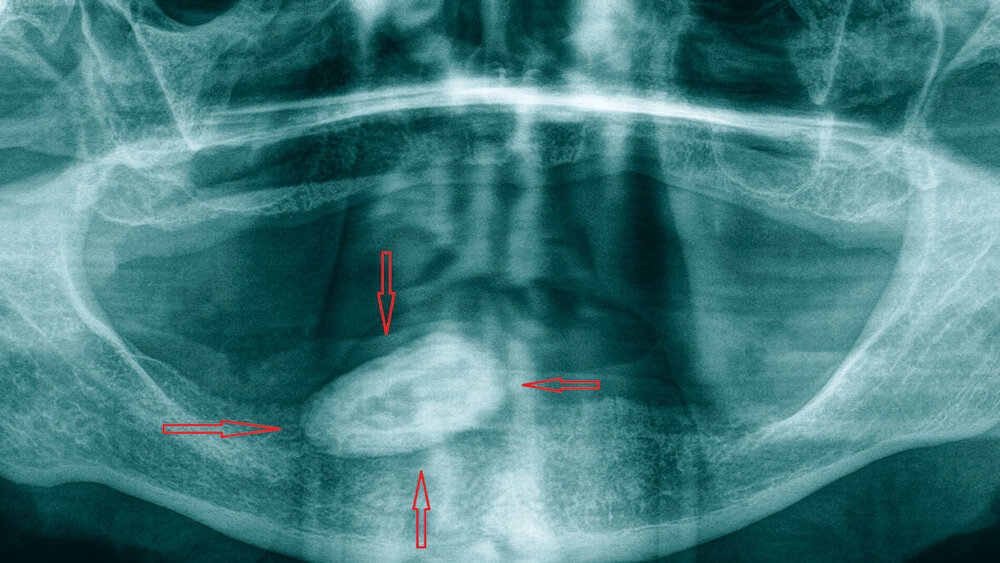

Die radiologische Diagnostik erfolgte mittels Panoramaschichtaufnahme (Abbildung 1). Auf dieser Röntgenaufnahme zeigte sich eine circa 27 mm x 15 mm große, hyperdense ovale Struktur, die sich über den rechten Unterkiefer projizierte.

Auf der Grundlage der Ergebnisse der klinischen und der radiologischen Untersuchung ergab sich mit allergrößter Wahrscheinlichkeit als Diagnose das Vorhandensein eines großen Sialolithen im Ductus submandibularis rechts. Überraschenderweise bestand trotz der außergewöhnlichen Steingröße keine klinisch relevante Beeinträchtigung des Speichelabflusses über den Ductus sublingualis. Auf näheres Befragen gab der Patient an, einmal vor einiger Zeit kurz anhaltende Schmerzen in dem Bereich gehabt zu haben.